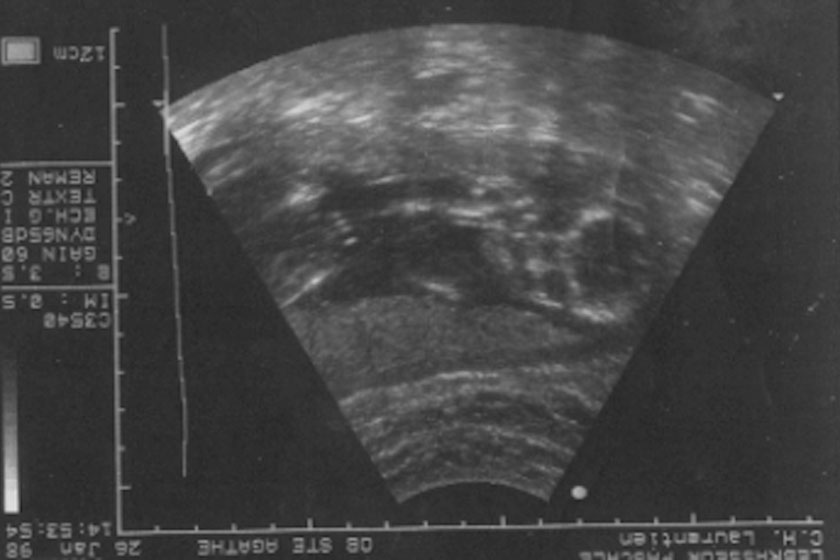

Quite early in this process I ended-up at the hospital with major cramps, because of the pregnancy, we had ultra-sounds done and the hospital staff was ready to terminate it all as they couldn’t see the fetus in my uterus. They assumed it was in one of my fallopian tube. They couldn’t see it anywhere but the bloodwork said I was pregnant. That day I learned that we were probably a good 3 weeks less advanced than we though.

I told the doctors that until they could prove that my life was in danger, they were not going to terminate my pregnancy. We scheduled a follow-up ultra-sound…

2nd ultra-sound! – they can see the fetus in the uterus but their is no “c.f.” ….. don’t you like it when doctors are talking about you but don’t want you to understand??? So, I asked, what’s a “c.f.”? The conversation was in French at the time and a c.f. stands for coeur foetal… my fetus’ heart…

From the previous ultra-sound, we knew I was at least 3 weeks behind the original delivery date but it wasn’t changed anywhere… so again I asked, is it possible that it is not formed yet? The answer was yes but we shouldn’t take a chance, we should terminate your pregnancy…. Wait what??? No!!!…. We should not terminate anything…. we should schedule another ultra-sound and see if the c.f. is there …

3rd ultra-sound! – here it is…. my fetus is in my uterus and has a tiny beating heart!